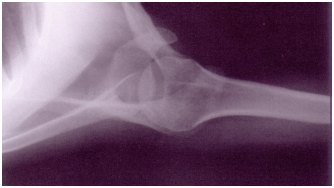

Observe:

A figura acima corresponde a uma incidência de